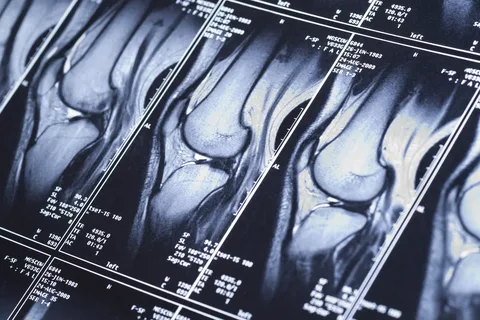

МРТ коленного сустава — самый информативный способ увидеть внутри структуры, которые недоступны обычному осмотру или рентгену. Статья расскажет, в каких ситуациях томография действительно нужна, как проходит процедура, что врач видит на снимках и как трактовать результаты. Также узнать больше можно на сайте https://spb.ramsaydiagnostics.ru/mrt/mrt-sustavov/mrt-kolennogo-sustava/